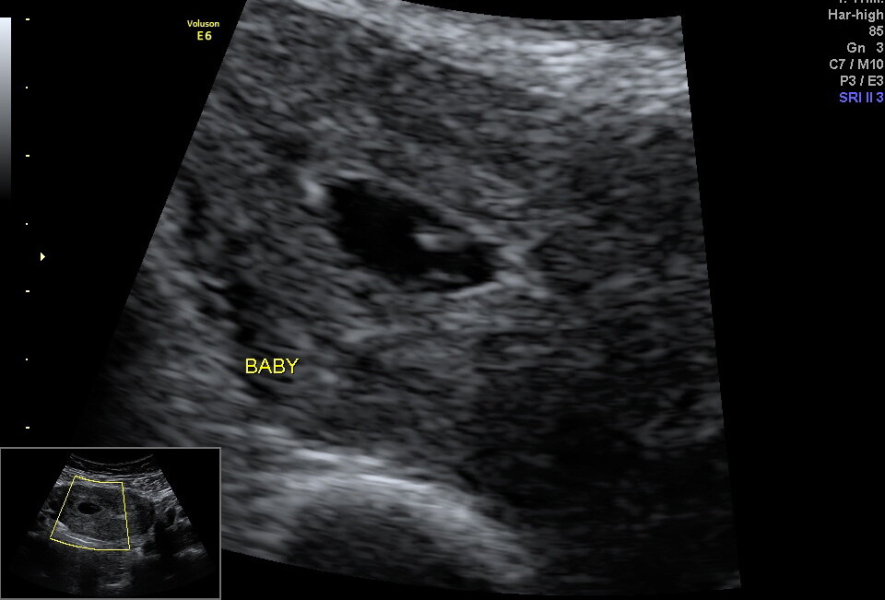

Measuring 6+1 🥹🥹🥹

They saw a little baby and a heartbeat. I got a little video but I can't post it here sadly!